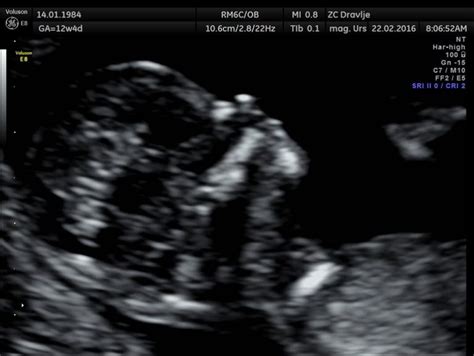

Pot do diagnoze kromosomske napake pogosto vodi preko rutinskih ali dodatnih preiskav v nosečnosti. Zgodnji ultrazvočni pregledi, ki potekajo med 11. in 14. tednom nosečnosti, so ključni pri ocenjevanju razvoja ploda. Posebno pozornost namenjajo meritvi nuhalne svetline - razdalje med kožo in podkožnimi tkivi na hrbtnem delu plodovega vratu. Povečana nuhalna svetlina je namreč eden najpomembnejših napovednih dejavnikov za morebitno kromosomsko prizadetost ploda. Večja kot je ta razdalja, večja je verjetnost za kromosomsko nepravilnost.

Poleg meritve nuhalne svetline lahko zdravnik v sklopu ultrazvočnega pregleda oceni tudi razvoj telesa ploda po posameznih organskih sistemih (glavica, hrbtenica, prsni koš, srce, trebuh, prebavni sistem, sečila, okončine), količino plodovnice in stanje posteljice. V nekaterih primerih se za še natančnejšo oceno tveganja uporablja tudi dvojni hormonski test, pri katerem se v materini krvi določita dva nosečnostna hormona: humani horionski gonadotropin in plazemski protein A. Če ultrazvočni pregled pokaže tudi obstoj nosne kosti, se lahko napovedna vrednost za odkrivanje kromosomsko drugačnih plodov zviša na več kot 90 %.